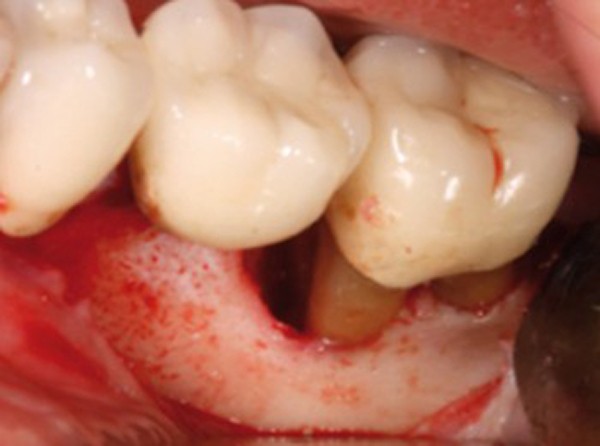

Ce sont des pathologies inflammatoires d’origine bactérienne, atteignant la gencive et le système d’ancrage des dents. Nous parlons de gingivites lorsque la maladie est circonscrite aux tissus gingivaux et parodontites lorsque la maladie a entraîné une destruction du système d’attache de la dent. Ces pathologies se développent par un processus inflammatoire en réponse à la flore microbienne de la cavité buccale. Et malheureusement, en l’absence de traitement, elles peuvent aboutir à la résorption complète de l’os et entraîner la perte des dents. Ce sont des maladies très fréquentes puisque la prévalence des parodontites chroniques atteint 50 % dans les pays industrialisés. De plus, il existe de nombreux facteurs aggravants, comme la consommation de tabac, la présence d’un diabète… et également des facteurs prédisposants héréditaires.

Les gingivites se reconnaissent facilement par la présence d’un saignement gingival spontané ou provoqué, et par un gonflement de la gencive. Les parodontites présentent ces mêmes signes, mais il existe une destruction du système d’attache, créant un repli entre les tissus mous et la dent nommé poche parodontale. Pour déterminer la gravité et l’étendue de la parodontite, nous réalisons…